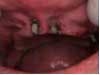

An 81-year-old female with stent placement 10 years ago taking no medications presented with a chief complaint that her old prosthesis broke, and she cannot chew and function. She had a previous bridge consisting of an implant in the No. 1 site combined with the natural teeth and implants in the 8, 9, 14, 15. No. 8, 9 implants were malpositioned with a 35-degree angle and significant mucogingival defects.

Under local anesthesia, a full thickness flap was elevated from the upper right to upper left posterior segments. Using a piezoelectric handpiece, a buccal window hinge osteotomy was elevated in the maxillary right posterior region. A mixture of DFDBA, anorganic bovine bone, and PRF was placed. A collagen membrane was used to cover the buccal window. Simultaneously, two puros J-block allografts were secured in the 5 to 7 and 10 to 12 region with stainless steel screws (1.6 x 8 mm screws). A mixture of DFDBA, anorganic bovine bone and PRF was placed over each area and covered with PRF sheet and a collagen membrane. Primary closure was obtained with CV-5 Goretex sutures. Healing was uneventful. After six months of healing, six straight implants were placed in sites 3, 4, 5, 6, 11, and 12. Healing abutments were placed at stage I. Healing was uneventful. After four months of healing, six custom abutments were fabricated by his dentist and cover screws were placed on implants 8 and 9 and converted into pontics.

Removing the implants would have created a large buccal defect, which would have created elongated pontics in the maxillary anterior region. The prosthesis was completed, and the patient is stable and highly appreciative of her ability to smile and chew.